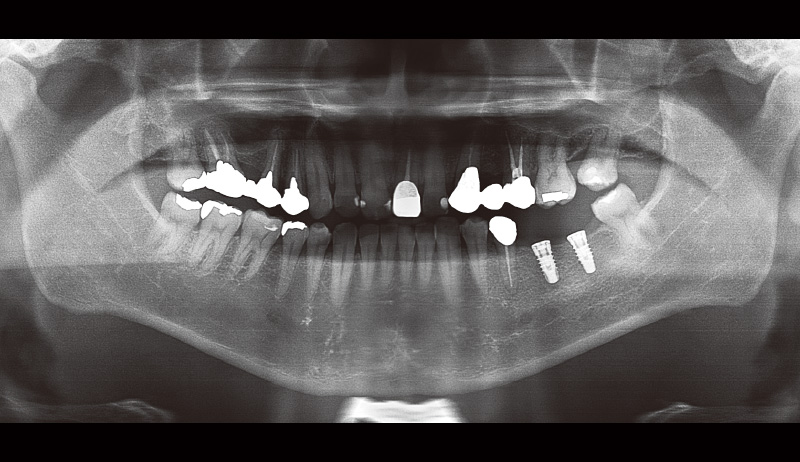

29歳男性、主訴:左下の奥歯が痛い。

₆の歯根破折による痛みがあり抜歯即時埋入を行った。φ6.0長さ8.0mmのSPIイニセルインプラント エレメントRCを選択(図3, 4)。埋入後3か月目で印象を行い補綴装置をセットした。抜歯即時埋入治療でも使いやすいインプラントだと実感した(図5)。

![[写真] 初診時のパノラマX線写真](/academic/dentalmagazine/wp-content/uploads/sites/2/2025/09/194-8_photo03.jpg)

図3 初診時のパノラマX線写真 -

![[写真] 抜歯即時埋入後のパノラマX線写真](/academic/dentalmagazine/wp-content/uploads/sites/2/2025/09/194-8_photo04.jpg)

図4 抜歯即時埋入後のパノラマX線写真 -

![[写真] 補綴装置セット後のパノラマX線写真](/academic/dentalmagazine/wp-content/uploads/sites/2/2025/09/194-8_photo05.jpg)

図5 補綴装置セット後のパノラマX線写真